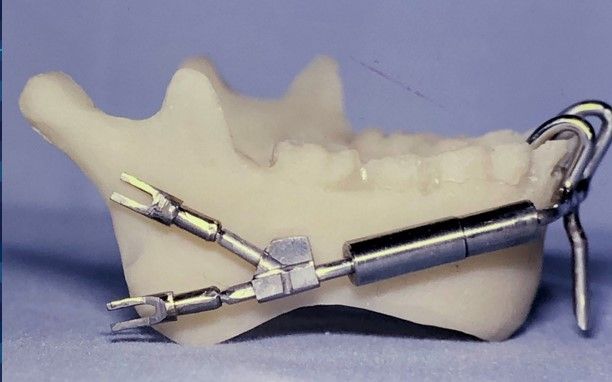

For over 30 years, Dr. Guerrero has made it his mission to improve the lives of his patients through specialized surgical care that restores function and comfort. Dr. Guerrero’s work embodies precision, compassion, and a dedication to patient well-being. Corrective jaw surgery is one of the advanced services offered, designed to address functional issues and enhance the quality of life for those who need realignment and reconstruction.